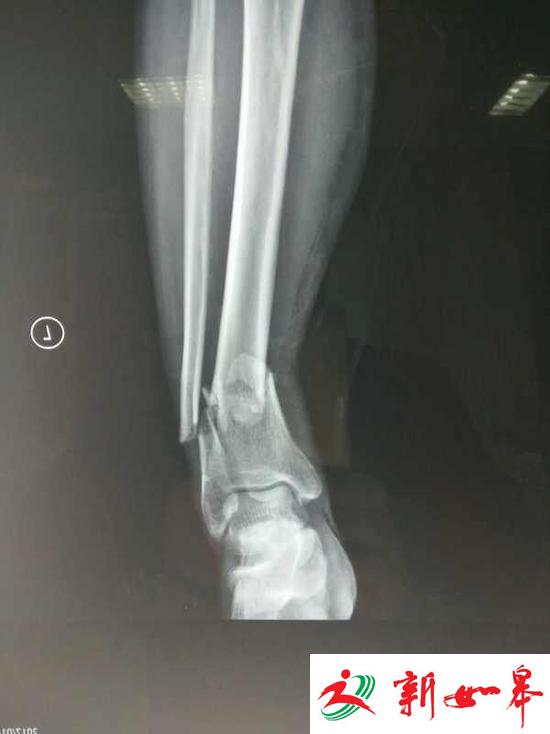

x片显示,靳淑海被撞后,小腿出现严重骨折。

靳琳告诉澎湃新闻,经过医院诊断,其父亲小腿有两处骨折,需要对外伤进行消炎消肿,大概10天后方可手术。